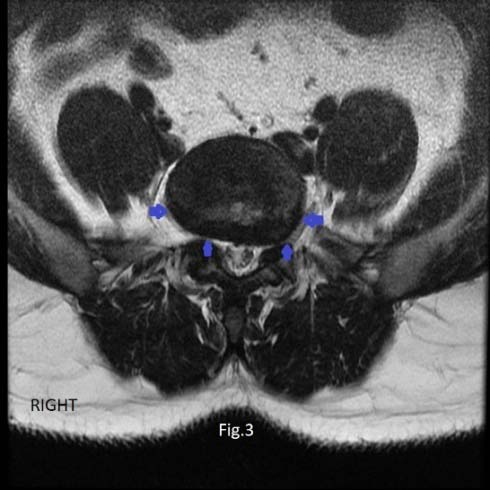

Amongst the 16 patients with PM partial attachment to the disc, 75.0% had disc herniation. From the 159 patients with nonattachment of the PM muscle, 60% suffered from disc herniation (Figure 3). Statistically, the difference in the prevalence of disc herniation in patients with partial attachment and those with nonattachment was insignificant, p=0.371.

When the PM partial attachment to the disc was analyzed separately at each disc level, at L5-S1 disc more patients were seen with partial PM attachment to the right side of the disc compared with the left side, 15 (8.5%) and 7 (4%) respectively.